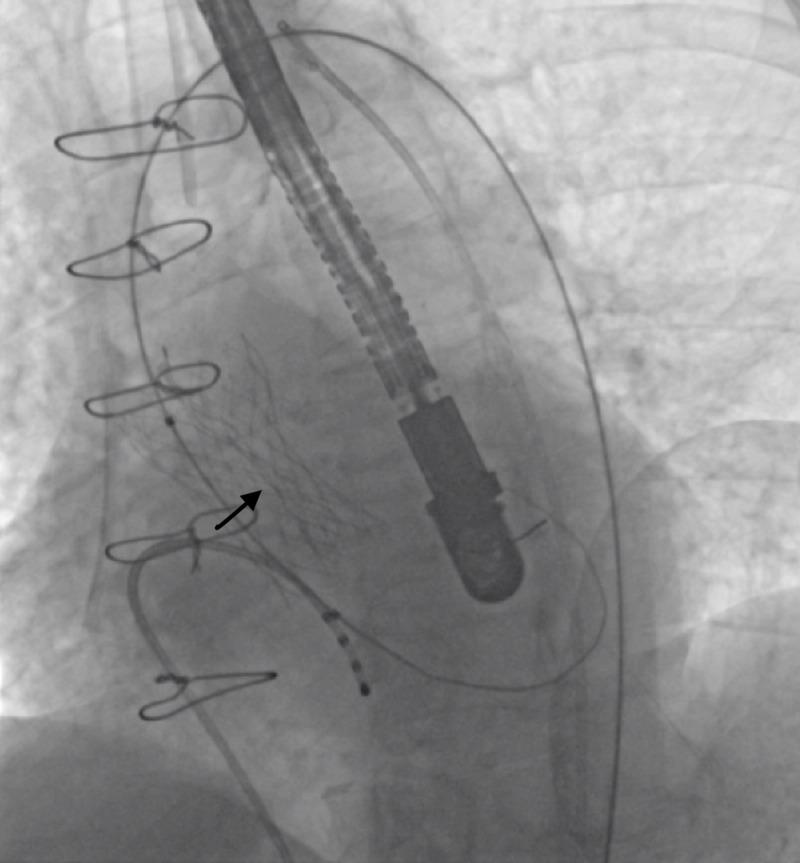

Transcutaneous aortic valve replacement (TAVR) has become a widely accepted minimally invasive approach for treatment of severe aortic stenosis. Self-expandable prostheses are commonly the device of choice, with excellent procedural success and durability. However, there have been several recent case reports of infolding of the self-expandable prosthesis during development with subsequent malfunction and need for further intervention. We present a case of self-expandable valve prosthesis infolding managed by balloon postdilation, and summarize the cases reported in the literature to date in an attempt to increase awareness of this serious technical problem and the factors associated with it.